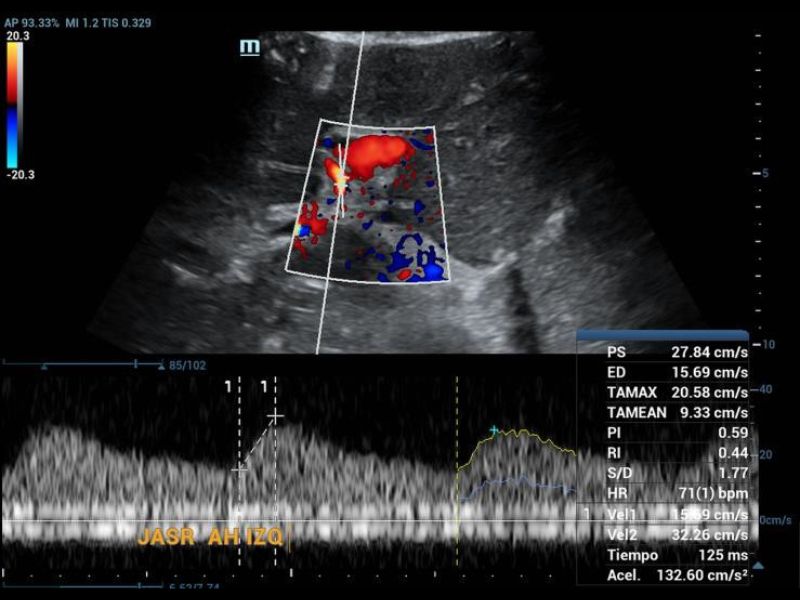

Doppler ultrasound, tardus parvus pattern in the left hepatic artery.

On examination of the grayscale graft, no findings of greater relevance were found in the parenchyma, but not when the vascular structures were evaluated in Doppler mode, since it was not possible to identify the right hepatic artery and the left was found with the morphology of tardus parvus (Figure 1), so the evaluation was directed towards a possible area of proximal stenosis, however, it wasn’t located.

Figure 1. Doppler ultrasound, tardus parvus pattern in the left hepatic artery.